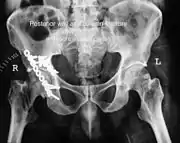

| Acetabular fracture as seen on plain X-ray |

Fractures of the acetabulum occur when the head of the femur is driven into the pelvis. This injury is caused by a blow to either the side or front of the knee and often occurs as a dashboard injury accompanied by a fracture of the femur.[1]